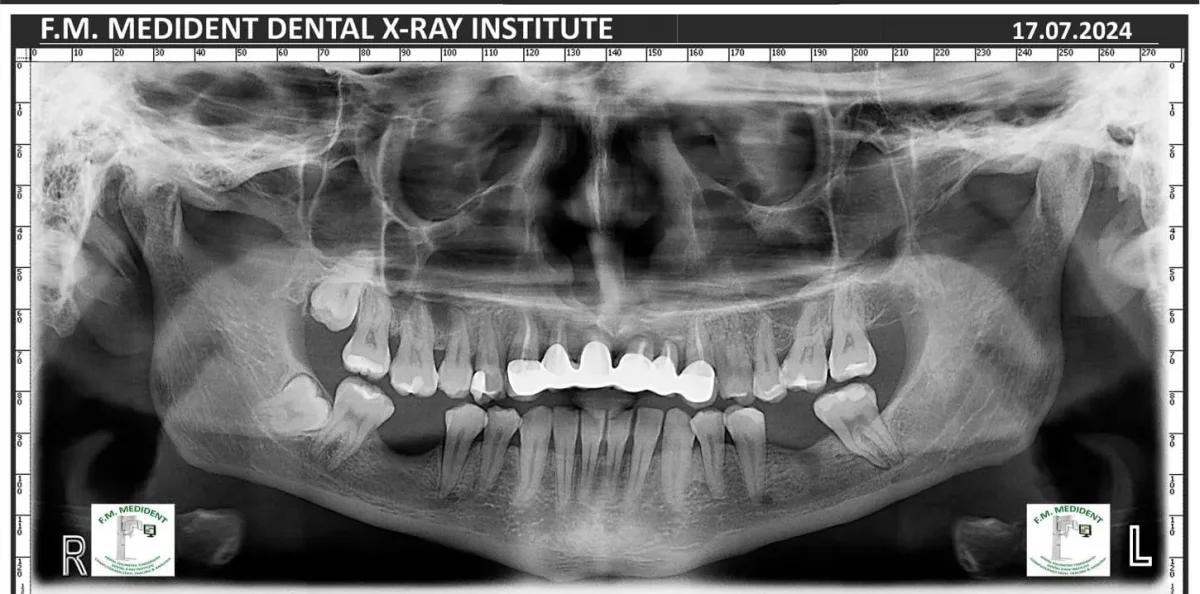

Cazuri reale înainte și după, din tratamente realizate în clinică.

Înainte

DupăExemple reale din cazuri tratate în clinică.